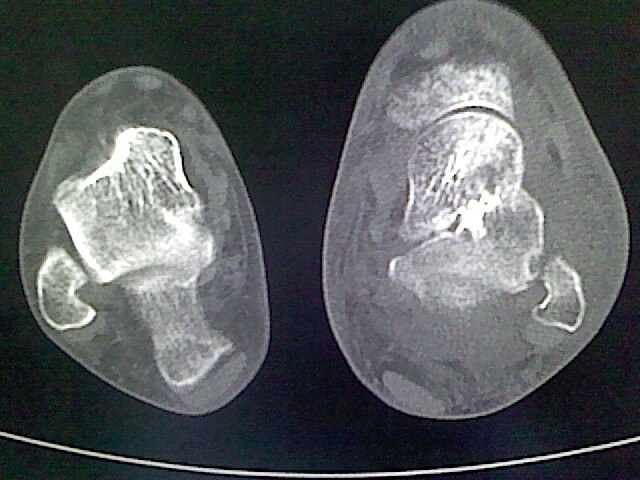

标题: CT16814:男,76岁,左小腿疼痛,不能站立 大家给看看 [打印本页]

男,76岁,左小腿疼痛,不能站立

本例骨质改变主要表现为滑膜或韧带区的骨侵蚀融解(胫腓联合区骨质破坏无硬化边),距骨后部骨质破坏区有硬化边及死骨样改变.所以,本例考虑关节结核可能性大,绒毛膜结节性滑膜炎多发于中年,且极少见于膝髋以外的关节,骨质硬坏也以压陷吸收为主,有明显的硬化边,骨膜增生呈结节状(可以mr鉴别),所以本例暂除外.

另不除外可引起相似表现的其他炎症如布氏杆菌性关节炎等